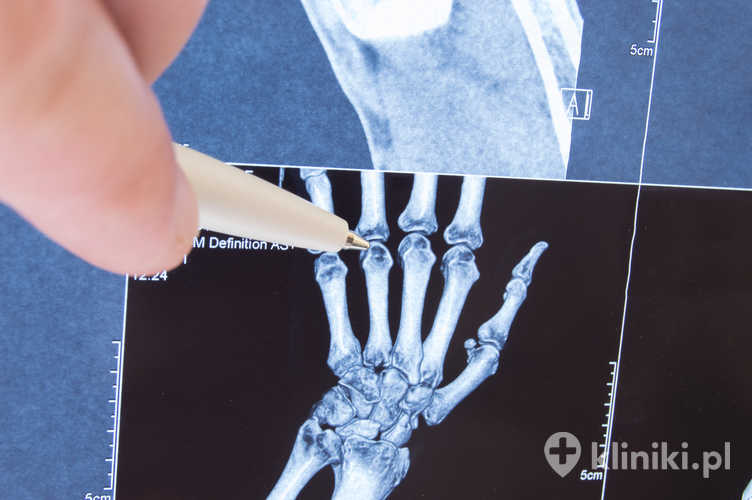

Choroba Dupuytrena jest schorzeniem należącym do grupy fibromatoz, znana jest również pod nazwą przykurczu Dupuytrena lub przykurczu rozcięgna dłoniowego. Charakteryzuje się powolnym bliznowaceniem i skracaniem łącznotkankowego rozcięgna dłoniowego, co prowadzi do przykurczu najczęściej palców IV i V.